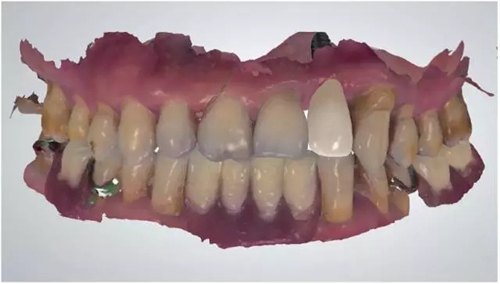

22缺失,21與23之間間隙大于12,切牙齦退縮明顯(圖1)。全景片示 22缺失處齒槽嵴高度和寬度及密度尚可(圖2)。

圖1 術(shù)前口內(nèi)照片